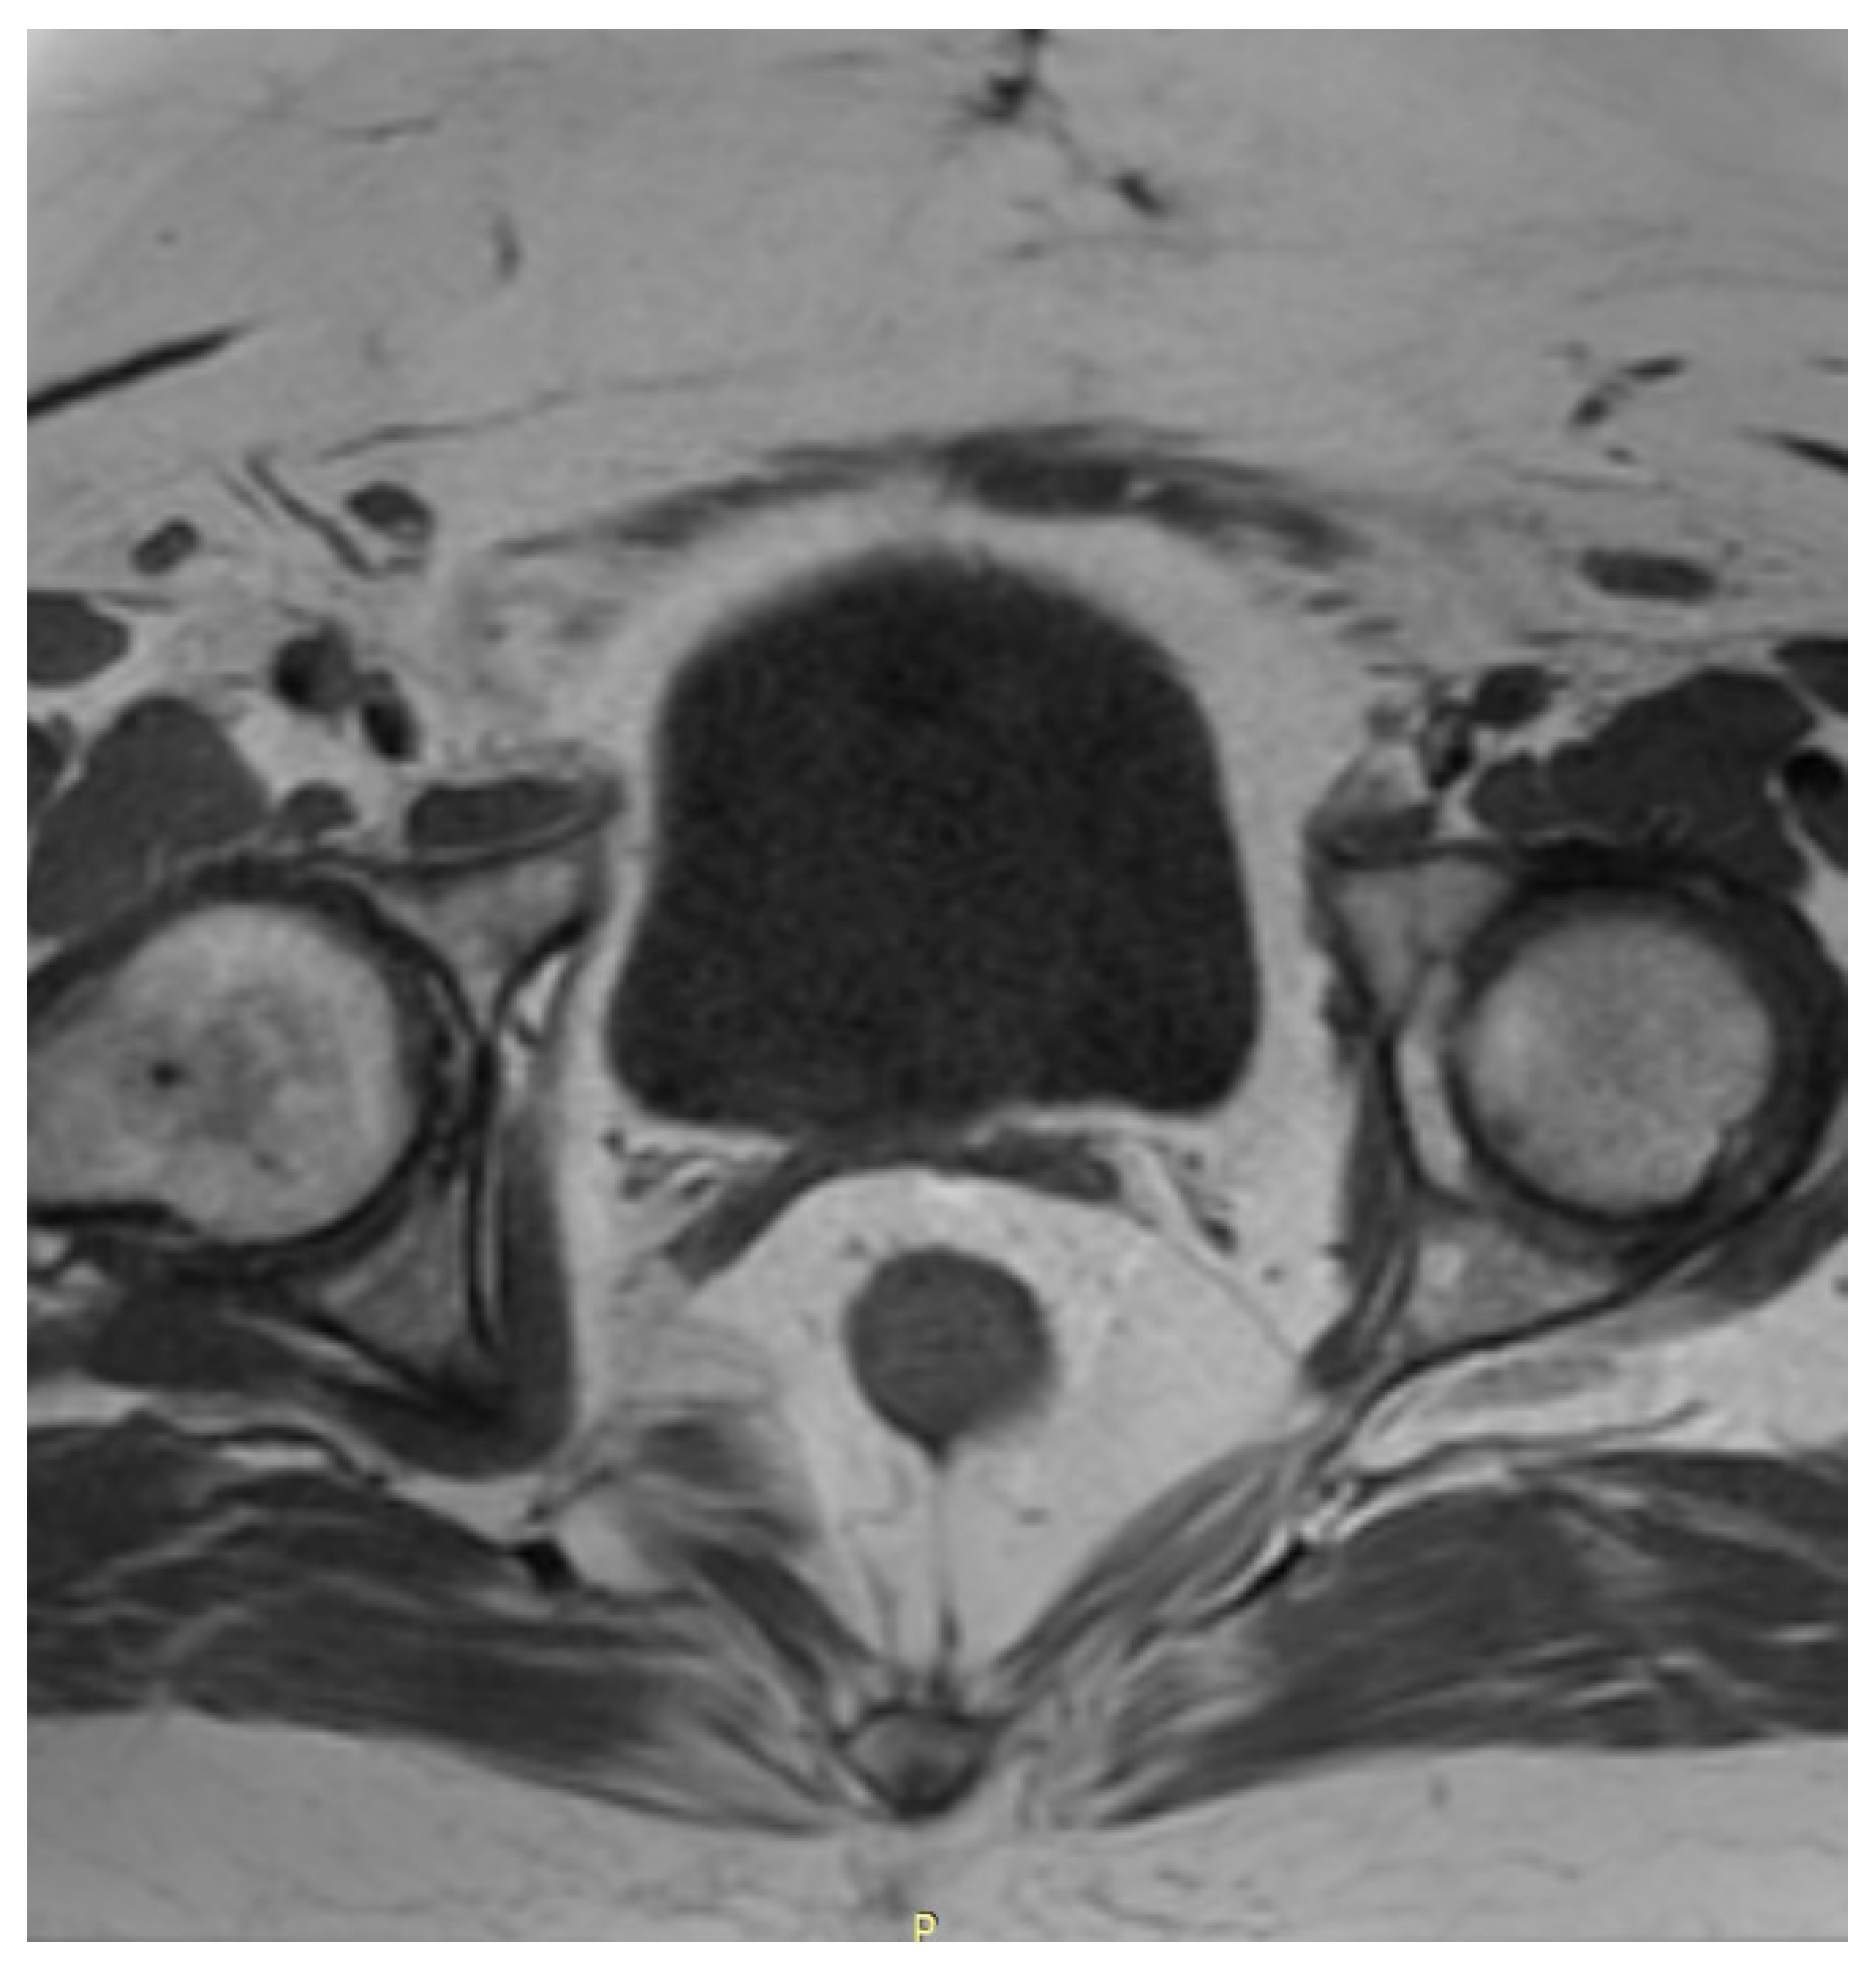

Three months after the initial hospitalization, the patient was admitted to the onco-logical gynecological ward. On admission she presented no irregularities in gynecological examination. A transvaginal ultrasonography of the uterus and pelvis was performed and a myoma, ca. 5 cm in diameter was found in the uterus wall. No other lesions were identified. A preoperative MRI of the abdomen and pelvis allowed identification of another 4 myomas in the uterus, with sizes from 7 to 54 mm, as shown in Figure 2.

Additionally, in the posterior wall of the cervix an irregular area (14 mm × 25 mm × 9 mm) was found, which was probably a malignant lesion. A single lymphatic node in the right inguinal area, with a diameter of 10 mm, was also identified. Remembering her symptoms and a history of a neoplasm in her family, the patient demonstrated a high level of anxiety towards her neoplasm. She expressed a wish to implement a radical treatment to ensure a disease-free result and this was also taken under consideration while choosing the therapeutic path.

After the surgery, the patient was regularly monitored in the outpatient clinic in the first year once every 3 months and afterwards once every 6 months. Three months after the surgery, a cytological examination was performed and no irregularities were found. The patient showed no symptoms and reported no complaints. One year after the surgery a CT scan of the chest and MRI of the pelvis and abdomen were performed—with no signs of neoplasm whatsoever. A postoperative MRI of the pelvis is shown in Figure 3.

Figure 3. A postoperative MRI of the pelvis in axial projection, performed 18 months after the Wertheim–Meigs operation. A vaginal stump is visible. No signs of recurrence are present.